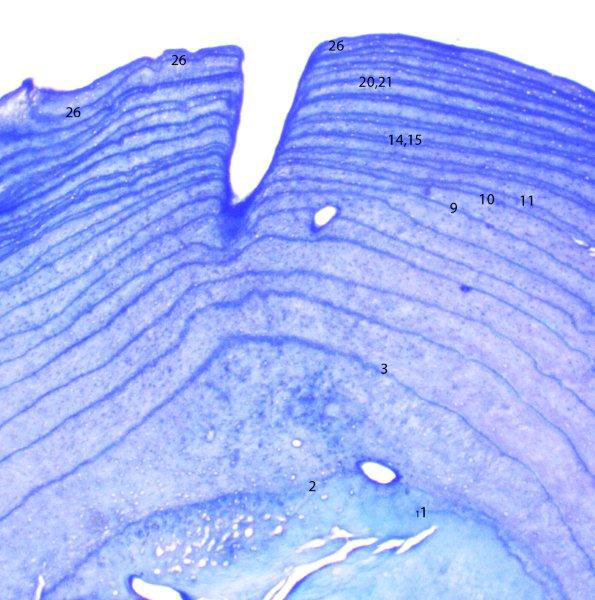

Midge's tooth section – 2009

Neugierige wollen es wissen. Lily Fans fragten:”Könnte Midge Shadows Mutter sein?” Wir hatten uns dasselbe gefragt. Im Rahmen der Obduktion, zogen wir einen Zahn und schnitten und färbten ihn. Wir mußten die Ringe zählen, um das Alter bestimmen zu können und die Abstände zwischen den Ringen, um zu sehen, wann sie Junge hatte. Wir haben festgestellt, daß Midge 1983 geboren wurde und 26 war, als sie starb. Sie war 4 Jahre älter als Shadow, die 1987 geboren wurde. Wenn Midge ihren ersten Wurf im Alter von 4 Jahren gehabt hätte, könnte sie Shadows Mutter sein. Doch der Abstand der Ringe erzählte uns, daß die kleine Midge keine überlebenden Jungen produziert hat bevor sie 1993 10 Jahre alt wurde.